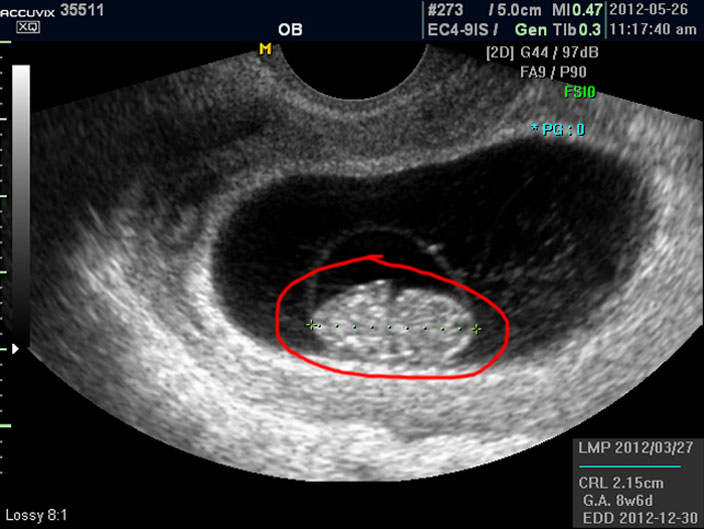

우선 첫번째로 보이는 사진에서 가운데 하얗게 보이는 것이 태아입니다.

우측이 머리 부분이고 좌측이 몸통 부분이며 초기 임신에서는 아기 머리가 몸통의 반정도로 상당히 큰 상태입니다.

태아의 크기는 우측 하단에 실제 크기가 나와 있지만 아래 사진에서 빨갛게 표시한 부분의 안에 보이는 눈금이 1cm입니다.

이런 기준이나 지표들이 표시되는 것은 초음파 장비마다 조금씩 차이가 있고 위치도 다르지만 대개 비슷한 모양이라 한가지를 알면 다른 기종에서도 감상에 그리 어렵지는 않습니다.